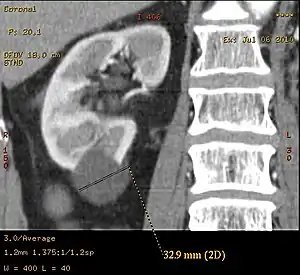

| Renal cyst | |

Diagnosis includes imaging with ultrasound, CT and/or MRI. The least expensive, non-invasive, and most reliable method is ultrasonography but smaller cysts may escape detection, while the resolution of CT and MRI will enable smaller cysts to be captured. However, the increased complexity and expense of CT and MRI is usually reserved for higher risk situations. MRI can be used to monitor the development of cysts and growth of kidneys.Genetic test can be applicable to those who have a family history of PKD but is expensive and fails to detect PKD in 15% of cases where it is present.